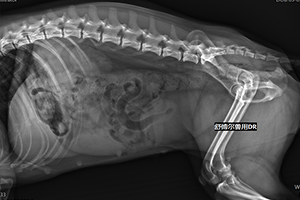

兽用DR –犬猫常见腹痛性疾病的鉴别诊断

犬猫腹痛,宠物临床常见症状,多为其他疾病的并发或继发所致。引起腹痛的疾病很多,需仔细鉴别。

腹痛、粪便干燥或停止主要见于便秘,其特点是频排粪但无粪便排出,腹痛或轻或重,腹部触诊有柱状或串珠状硬物,伴肠鼓气。X线检查腹腔内有高密度影像和鼓气。

6、肠梗阻:腹部触诊有不规则硬物,肠音低。X线检查见高密度异物,钡餐检查肠道不通。